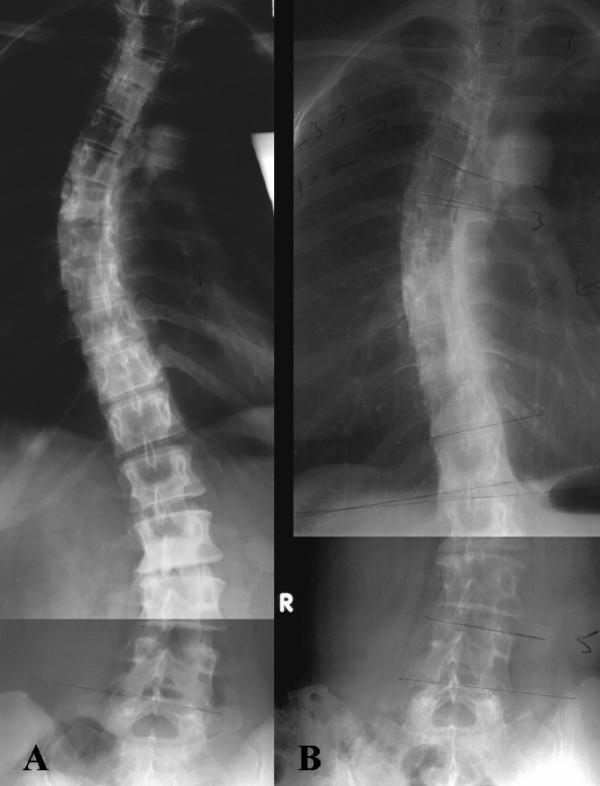

A diagnosis of thoracic scoliosis (Cobb angle 45 degrees) with pectus excavatum and thoracic hypokyphosis in a female patient (DOB 9/17/52) was made in June 1964. Immediate spinal fusion was strongly recommended, but the patient elected a daily home exercise program taught during a 6-week period of training by a physical therapist. This regime was carried out through 1992, with daily aerobic exercise added in 1974. The Cobb angle of the primary thoracic curvature remained unchanged. Ongoing clinical symptoms included dyspnea at rest and recurrent respiratory infections. A period of multimodal treatment with clinical monitoring and treatment by an osteopathic physician was initiated when the patient was 40 years old. This included deep tissue massage (1992-1996); outpatient psychological therapy (1992-1993); a daily home exercise program focused on mobilization of the chest wall (1992-2005); and manipulative medicine (1994-1995, 1999-2000). Progressive improvement in chest wall excursion, increased thoracic kyphosis, and resolution of long-standing respiratory symptoms occurred concomitant with a >10 degree decrease in Cobb angle magnitude of the primary thoracic curvature.

1964年6月,一名女性患者(出生日期:1952年9月17日)被诊断为胸段脊柱侧弯(Cobb角45度),伴有漏斗胸和胸段脊柱后凸减小。强烈建议立即进行脊柱融合手术,但患者选择了由物理治疗师在为期6周的训练期间教授的每日家庭锻炼计划。该方案一直执行到1992年,1974年增加了每日有氧运动。胸段主弯的Cobb角保持不变。持续的临床症状包括静息时呼吸困难和反复呼吸道感染。患者40岁时开始了一段由整骨医生进行临床监测和治疗的多模式治疗期。这包括深层组织按摩(1992 - 1996年);门诊心理治疗(1992 - 1993年);以胸壁活动为重点的每日家庭锻炼计划(1992 - 2005年);以及手法医学治疗(1994 - 1995年,1999 - 2000年)。胸壁活动度逐渐改善、胸段脊柱后凸增加以及长期呼吸道症状的缓解与胸段主弯Cobb角大小降低超过10度同时出现。